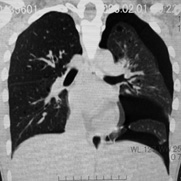

secondCT.jpg

初診時CT(左)から2年後のCTでは肺の嚢胞化が著明となっている。